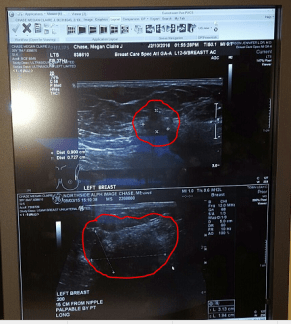

I am extremely visual, so I can still see her walking in after the results of the ultrasound on 2/11/16. She actually didn’t walk in; she practically danced in with her hands in the air and huge smile on her face. Before she could even speak, I started crying. She told me that all that monster chemo worked and my tumor had shrunk significantly. She gave me such a warm hug and then asked if I wanted to see the ultrasounds. I started crying again when I saw how super huge it was in September of 2015 (bottom image) and the dramatic difference in size on that February day (top image). I would look at this constantly. It gave me the strength to make it through the final two treatments. It was finally time to schedule surgery.